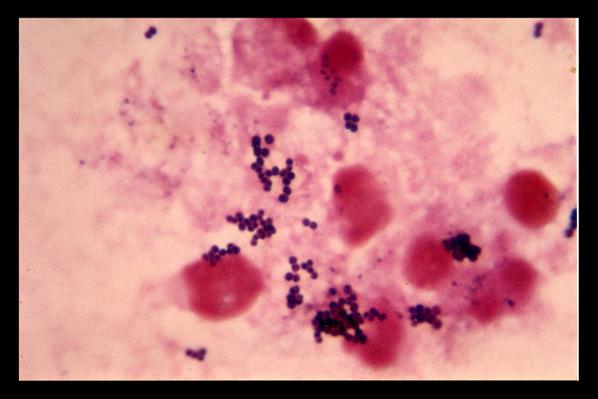

به گزارش رویترز، در دهههای اخیر بر شمار باکتریهای مقاوم در برابر داروهای شناخته شده افزوده شده که باعث نگرانیهایی در خصوص سلامت عمومی جهانی شده است. مقاومت باکتری بیماریهایی چون سل یا سوزاک میتواند باعث اپیدمیهای جهانی شود.

این تحقیق توسط گروهی از دانشمندان بریتانیایی به سرپرستی دکتر چنگجیان دانگ در دانشگاه آنگلیای شرقی انجام شده است. این تیم تحقیقاتی با ابداع روشی برای بررسی دیواره سلولهای باکتریهای مقاوم در برابر آنتی بیوتیکها، دریافتند که سیستم دفاعی این سلولها چگونه در برابر آنتی بیوتیکها عمل میکند.

دکتر دانگ میگوید: «یک سیستم دفاعی در این سلولها مانند دروازههای یک دیوار عمل میکند و نمیگذارد که دارو بر آن اثر کند.»